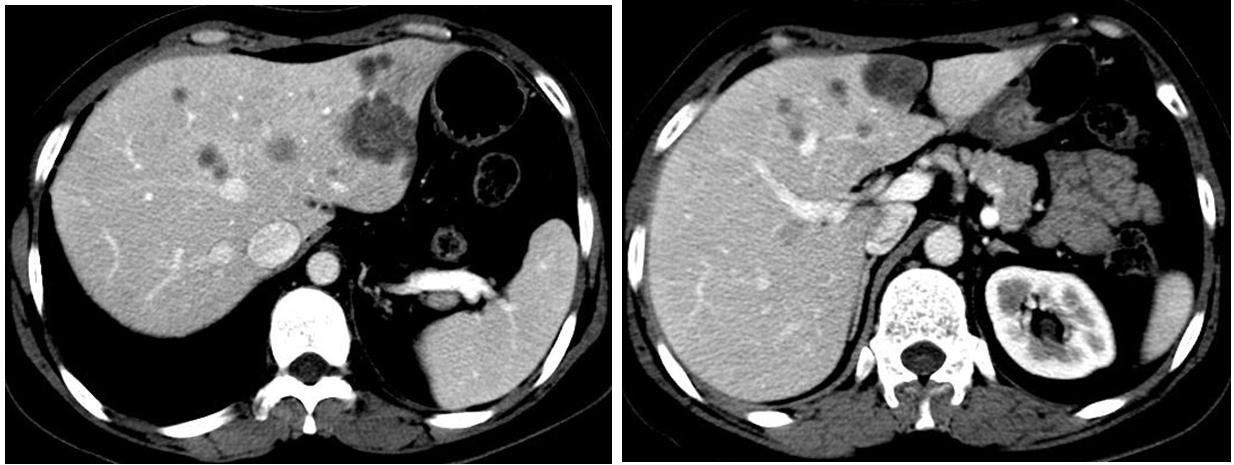

图1 肝转移病灶

本例患者肝内出现新发、多发病变,说明全身病变处于活跃进展期,这种情况下不能给予肝脏放疗。事实上,放疗对肝转移癌效果很好,但本例患者不适合局部放疗,应该以全身内科治疗为主。待病情稳定、肝脏病变由多个缩小为1~3个,且病变不大时可以考虑放疗。

房辉教授:CT报告提示肝脏病灶明显好转,仅存一个大小约1.1cm的病灶,同时肺部病灶较稳定,如果肝功能达到A级,可以给予肝脏的局部放疗。